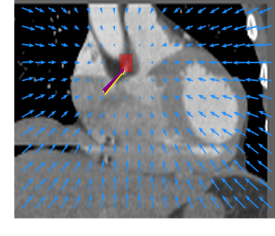

Finally, the proposed network was evaluated for the detection of five additional landmarks: the left coronary ostium, the bifurcation of the LM into the LAD and the LCx, and the origin of the left, non-coronary, and right aortic valve commissures (see Fig. 2). Fig 3 shows vector fields visualizing the predicted displacement vectors in three viewing planes in an image from the test set (for more results, see Appendix). Table 3 lists the Euclidean distance errors between the predicted landmark locations and the reference landmark locations. In addition, box-and-whiskers plots are shown in Fig 4. The best results were obtained for the origin of the right aortic valve commissure. Detection of the origin of the left aortic valve had the most narrow distribution. Outliers were seen during detection of the right ostium, the bifurcation of the LM, and the origin of the non-coronary, and the left aortic valve commissure.

Refer to caption Refer to caption Refer to caption

Figure 3: Vector fields visualizing the predicted displacement vectors in the axial, coronal, and sagittal plane in an image from the test set where detection of the right coronary ostium was performed. The magnitudes of the vectors should point at the right ostium, but they are rescaled for visualization purposes. The red squares indicate posterior probabilities larger than 0.5, obtained by the classification network for image patches. Reference and computed landmark annotations are indicated with a yellow and purple arrow, respectively.